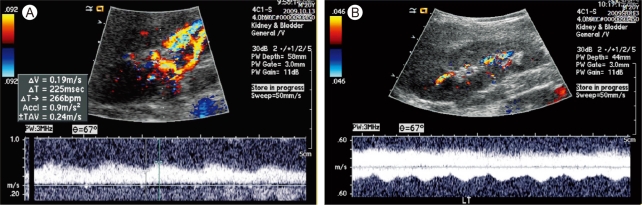

A 21-year-old male with secondary hypertension was referred to our facility by a general physician. The patient had no family history or risk factors for hypertension. During the physical examination the patient's blood pressure (BP) measured 190/110 in both arms and no cardiac murmur or bruit was detected. Renal Doppler sonography was performed to identify the potential cause of secondary hypertension, specifically renal artery stenosis. Tardus-parvus pulse waves were noted in both renal intra-arteries (Fig. 1A and 1B); however, a subsequent abdominal computed tomography (CT) did not show any evidence of renal artery stenosis and both adrenal glands looked normal. There was a noted tortuous and engorged superior-epigastric artery along the abdominal wall (Fig. 2).

Figure 2

Abdomen contrast computed tomography shows tortous and engorged superior epigastric artery along the abdominal wall (arrows).

Renal Doppler sonography is a useful and frequently used tool to evaluate secondary hypertension. When bilateral tardus-parvus wave patterns are detected, bilateral renal artery stenosis, aortic stenosis, and COA should be considered. To differentiate between COA and bilateral renal artery stenosis, the pulse wave of the aorta should be checked, which is superior to the renal artery. If the aortic pulse wave also shows tardus-parvus patterns, it can either be COA or AS [1]. Additionally, engorged collateral circulations, such as in the internal thoracic artery, intercostal artery, or superior epigastric artery, can help in the diagnosis of COA [2].